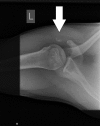

Results: From 2005 to 2017, a total of 19 cases of pectoralis major ruptures occurred in military academy cadets. Patients ranged in age from 19 to 23 years, with a mean age of 20 years. All injuries occurred during sports activity, with bench press as the most common mechanism of injury (n = 10; 53%). The most common rupture location was the musculotendinous junction (n = 10; 53%), followed by pectoralis major tendon insertion (n = 8; 42%), and only 1 bony avulsion was noted. Physical activity performance following the rupture was negatively affected. The mean ± SD number of push-ups preinjury was 73.20 ± 12.10, which decreased following injury and surgery (66.50 ± 11.98; P = .037).